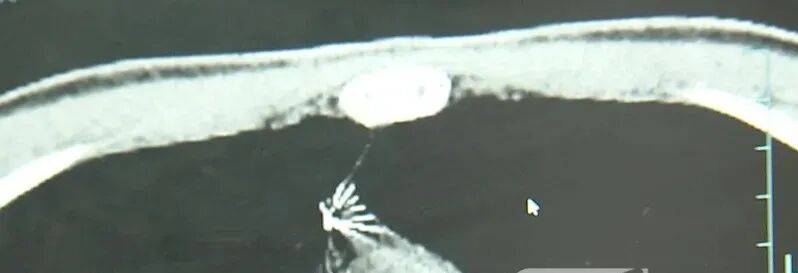

近日,安徽17岁小伙小陆参加征兵体检,胸片结果显示:胸腔内有一处金属高密度影,形态细长,像一根针双环传动股票。

进一步的CT检查确认,异物是一枚金属针,斜插在肺组织内,位置十分凶险双环传动股票。

杭州市第一人民医院心胸外科副主任冯兴说:“我们看到这个针的尖锐部,正好指向他体内的一个大血管,边上是上腔静脉和胸主动脉,因此这个针稍有不慎,就有可能造成周边血管的损伤,甚至危及生命双环传动股票。”